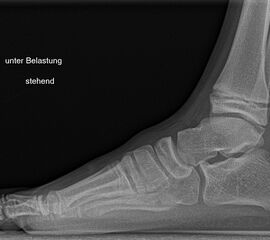

Diagnostisches Vorgehen

Damit die minimalinvasive Fußchirurgie zur Korrektur kindlicher oder jugendlicher Fußdeformitäten erfolgreich angewendet werden kann, erfordert die präoperative Diagnostik Röntgenbilder in drei Ebenen am stehenden Fuß. Röntgenbilder ohne Belastung des Fußes sind nicht zielführend. Im Fall von schweren Rückfußdeformitäten wird das obere Sprunggelenk in die radiologische Diagnostik mit einbezogen in Kombination mit der Rückfußaufnahme unter Belastung („Saltzman View“). Das OSG wird in zwei Ebenen geröntgt. Die streng seitliche Aufnahme des OSG kann bei den komplexen Fußdeformitäten mit der seitlichen Aufnahme des Fußes unter Belastung kombiniert werden. Das reduziert die diagnostische Strahlenbelastung der Kinder.

Indikationen für die beschriebenen Röntgenaufnahmen sind Klumpfußdeformitäten zur Beurteilung eines „flat top talus“ oder neurologische Grunderkrankungen mit varischer Fersenstellung wie zum Beispiel bei HSMN (Hereditäre Sensorische Motorische Neuropathie).